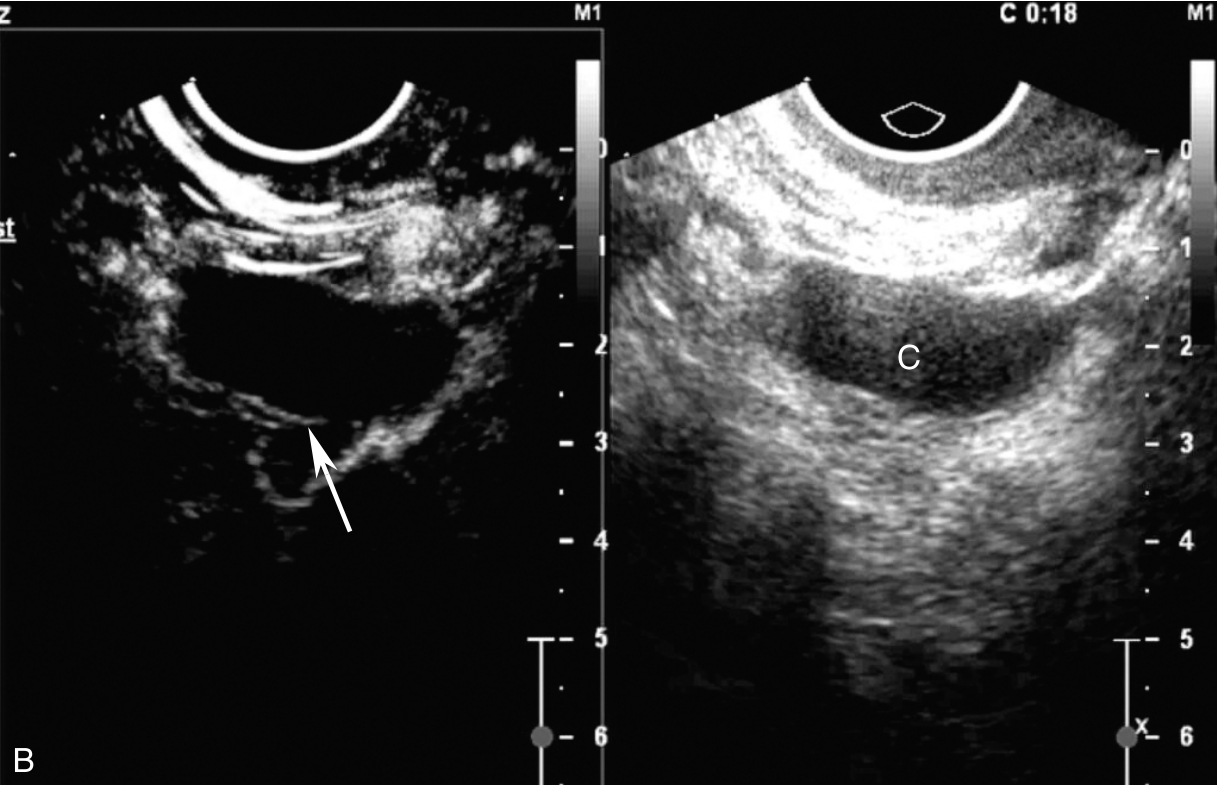

经阴道超声检查见图3-12-2。子宫前位,宫体大小为4.6cm×6.5cm×5.6cm,内膜居中,厚0.2cm(单层),肌壁回声欠均匀,未探及明显异常血流。宫颈查见囊性占位,最大径约3.1cm,液体欠清亮,周边未探及血流信号。右卵巢上查见囊性占位,大小为3.0cm×1.6cm×2.5cm,囊液欠清亮,囊壁可探及血流信号。左附件区未见占位。超声检查结果:右卵巢上囊性占位(多系良性),子宫颈腺囊肿。

图3-12-2 常规超声声像图

A.前位子宫的矢状切面;B.子宫横切面;C.右附件区囊性占位;D.宫颈囊性占位。UT:子宫;C:囊肿;Cx:宫颈。